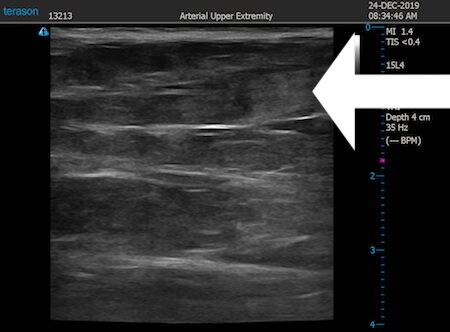

いつものように3Dタッチビュー(超音波)で

皮下脂肪層を評価してみましょう。

同様に下腹部 ↓ ↓ ↓

↓ ↓ ↓